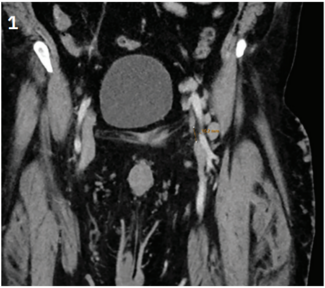

Dr. Kern and his expert colleagues discuss a case of pectus excavatum, a structural deformity of the anterior thoracic wall in which the sternum and rib cage produce a caved-in or sunken configuration of the chest. It can be congenital at...